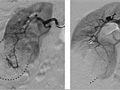

An angiogram is an X-ray test that uses dye and a camera to take pictures of the blood flow in an artery or a vein. An angiogram can be used to look at the arteries or veins in the head, arms, legs, chest, back, or belly. This test is done to look for problems in the arteries or veins.

During an angiogram, the doctor will put a thin, flexible tube into a blood vessel in your groin or arm. This tube is called a catheter. The doctor guides the tube to the blood vessel that will be studied. Then a dye is injected through the tube to make the area easier to see. X-rays or pictures are taken of the area.

When the catheter is in place, the dye is injected through it. You may be asked to take a breath and hold it for several seconds. Several X-ray pictures will be taken one after another. These will be available right away for your doctor to look at. You need to lie very still so the pictures are clear. More pictures may be taken.